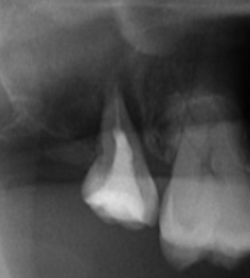

移植の成否を左右する要素の一つが、移植歯が口の外に出ている時間(口腔外時間/extra-alveolar time)です。歯根膜細胞は乾燥や機械的損傷に弱く、時間が延びれば延びるほどリスクが上がります。

臨床でも「短く、湿潤を保ち、触りすぎない」が原則です。

ここで重要なのが、移植特有の難しさです。

移植する歯根は、インプラントに比べて形が複雑で大きいことが多く、

しっかり適合させるために移植床の形成に時間がかかる

→ 試適回数が増え、歯根膜が傷む

→ 歯根吸収・アンキローシスの確率が上がる

つまり、移植の難しさは「外科的に入れること」ではなく、歯根膜のダメージを最小化しながら“適合させきること”にあります。

リスクを最小化する現代的アプローチ:CT×3Dレプリカ(ドナー歯模型)

近年注目されているのが、CTデータからドナー歯の3Dレプリカ(模型)を作成し、移植床形成・適合を事前に詰めておく方法です。

狙いは明確です。

- 移植床の形成をレプリカで完結させる

- 実歯(ドナー歯)を抜いた後は、最小回数・最短時間でフィットさせる

- 口腔外時間を短縮し、歯根膜への機械的損傷を減らす

「移植床に合わせるために、移植歯を何度も出し入れする」

この一番避けたい状況を、デジタルが解決し得る——それが、移植が再注目される大きな理由です。

1)精密診断(CT)

ドナー歯(親知らず等)の形態、根の湾曲、欠損部の骨量・形態を評価し、移植が成立する条件かを判断します。